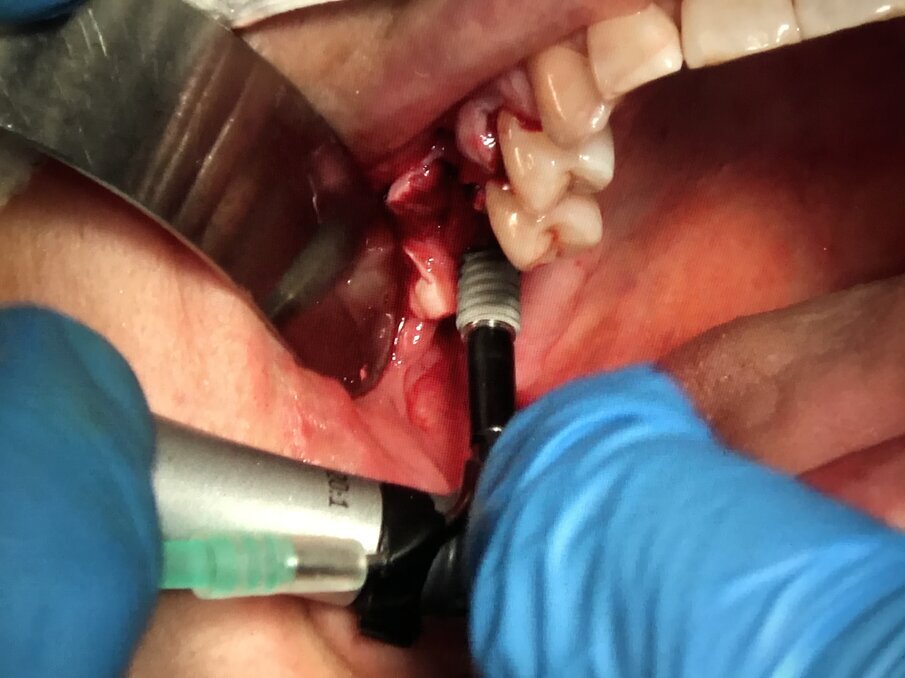

Fig. 16 - Sinus lifting: elevazione membrana Schneideriana con Piezosurgery.

Fig. 17 - Sinus lifting: inserzione di impianti endoossei Multysytem.

Fig. 18 - Sinus lifting: dopo l’inserzione di due impianti Multysytem si riempie la neo-cavita sotto Schneideriana con I-PRF addizionato a xenoinnesto osseo.

Fig. 19 - Sinus lifting: chiusura della finestra ossea con membrana di gel piastrinico A-PRF.